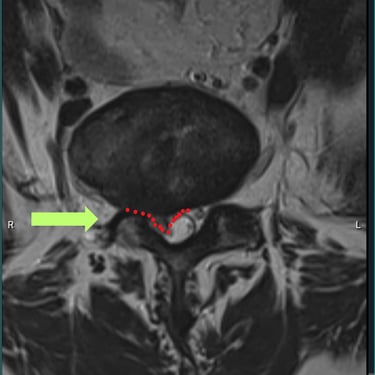

🧠 Listesis L4–L5 con Estenosis Severa: Estabilización con Fijación Transpedicular (FTP) y Fusión Intersomática Transforaminal (TLIF)

La listesis L4–L5 con estenosis severa provoca dolor lumbar e inestabilidad con compresión nerviosa. La fijación transpedicular (FTP) y la fusión intersomática transforaminal (TLIF) permiten descomprimir el canal espinal, estabilizar la columna y mejorar la función de forma segura y progresiva.